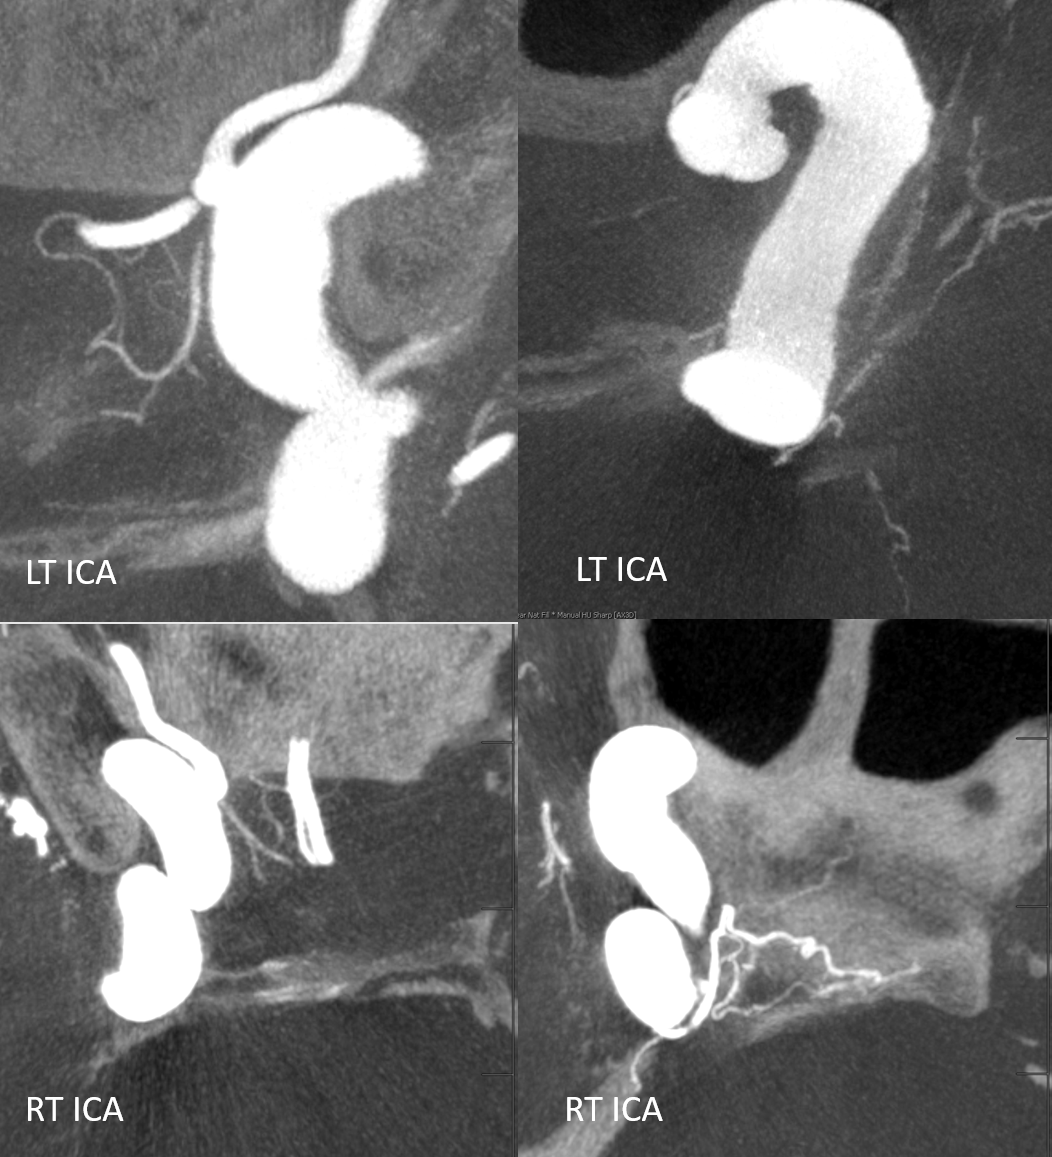

Another interesting topic. Courtesy Eytan Raz MD PhD. Hypophyseal Aneurysm, post PED

Follow up — notice a “lower” origin of the ophthalmic now, and a small vessel (arrow) from the medial wall, adjacent to the new ophthalmic ostium.

What happened to the ophthalmic origin? See Pipeline Device Properties page for more into. Basically, the Pipeline is not fully apposed to the ophthalmic ostium, creating a secondary communication between the aneurysm and the ophthalmic — essentially incorporating the ophthalmic ostium into the aneurysm. As the aneurysm shrinks, the flow to ophthalmic is reorganized. Other examples are on the Pipeline page.

Fine. But what about the little branch — the superior hypophyseal artery?

Whats interesting is that the superior hypophyseal was part of the aneurysm. Now that the aneurysm has shunk its ostium has come to appose the Pipeline, and its flow is preserved. Other interesting things are there too.

Patent Superior Hypophyseal artery (arrow) post Pipeline Embolization Device placement (6 months post).

The patency of jailed vessels post technically optimal flow diversion (good wall apposition, good antiplatelet coverage) is principally determined by the collateral potential of the jailed artery. Ophthalmics occlude, asymptomatically in pretty much all cases, because of rich external collateral networks. One way to estimate collaterals is to see what happens to arteries post flow diversion. Below, pre-treatment top row shows two patent superior hypophyseals (arrows) and ophthalmic. Six months later (bottom row), the aneurysms and ophthalmic are closed, while superior hypophyseals remain patent.

Another Example

Note stenosis at the proximal segment of the device due to the proximal edge terminating on the curve of the anterior genu (dashed arrow). This is a kind of T-bone configuration which usually heals with a stenosis.